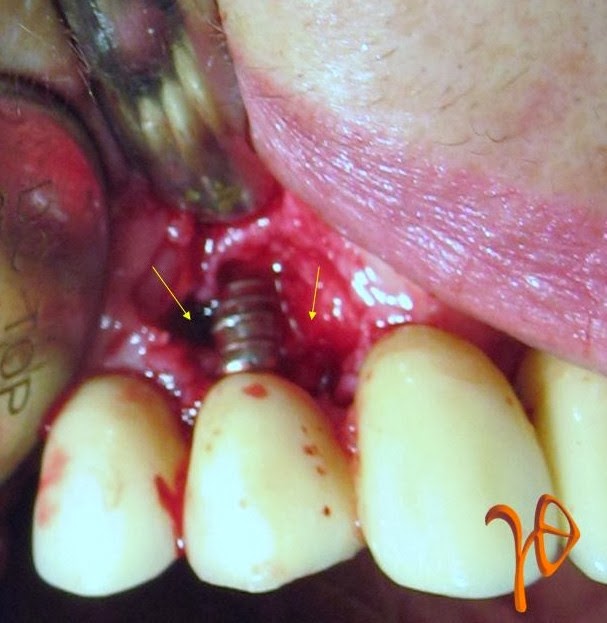

Οι πιο συχνές βλάβες από ερεθισμό στο στόμα είναι τα αντιδραστικά ινώματα (Εικόνες 4 και 5).

Εικόνα 4. α. Ίνωμα της υπερώας από χρόνιο ερεθισμό ολικής οδοντοστοιχίας (βέλος), β. Μετά την χειρουργική του αφαίρεση.

Εικόνα 5. α. Ίνωμα της παρειάς από χρόνιο ερεθισμό της σύγκλεισης στην περιοχή (βέλος), β.Μετά την χειρουργική του αφαίρεση.